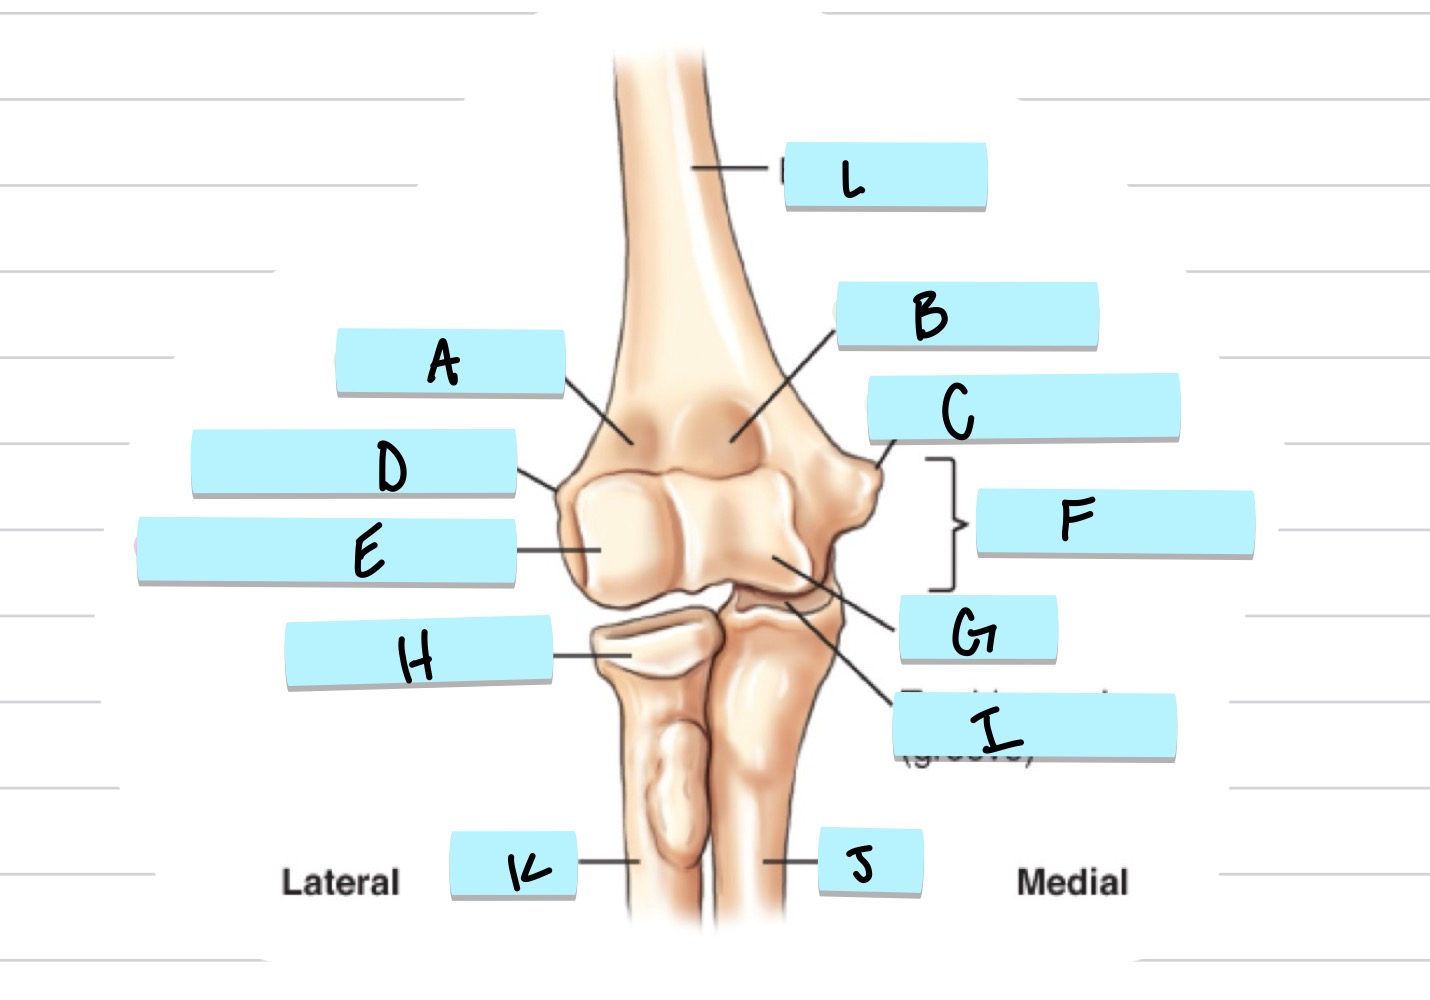

<p>what is A</p>

what is A

scaphoid

49

New cards

<p>what is B</p>

what is B

lunate

50

<p>what is C</p>

what is C

triquetrom

51

<p>what is D</p>

what is D

pisiform

52

<p>what is E</p>

what is E

trapezium

53

<p>what is F</p>

what is F

trapezoid

54

<p>what is G</p>

what is G

capitate

55

<p>what is H</p>

what is H

hamate